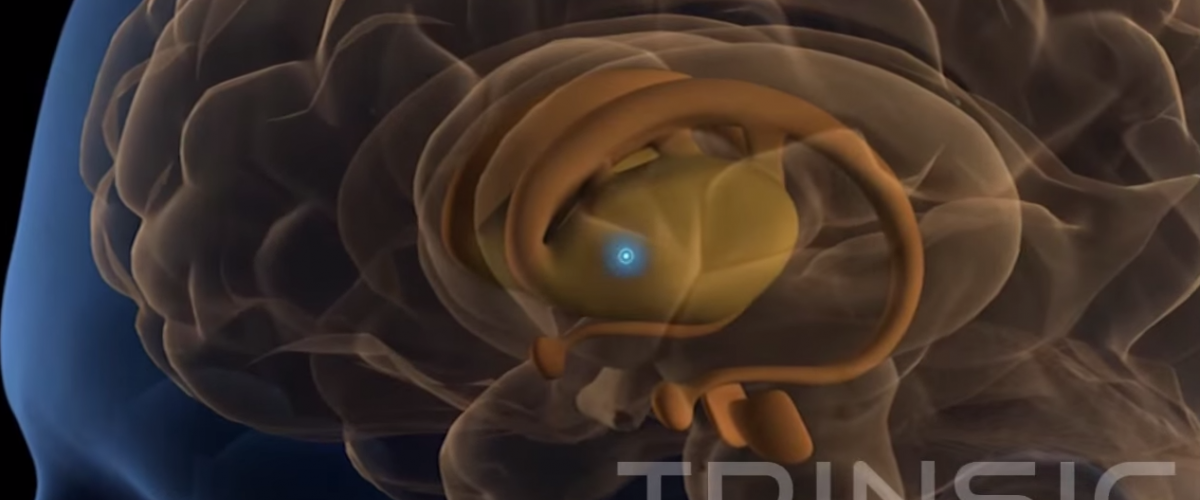

The Nerve Growth Factor in Alzheimer’s Disease Study Alzheimer’s Disease affects millions of people worldwide, the main symptoms are caused by the degeneration of brain cells that control memory and thinking.

These cells are originated in the nucleus pulposus and communicate with the hippocampus and cerebral cortex.

As these cells to degenerate they lose their ability to produce acidic alkaline and communicate with other cells, current medicines improve Alzheimer’s symptoms for several years, but become ineffective as the disease progresses.

An experiment with bio pharmaceutical drug called CERE-110 has been tested in over 35 people with Alzheimer’s disease. CERE-110 is intended to restore damaged cholinergic cells and protect them from further degeneration.